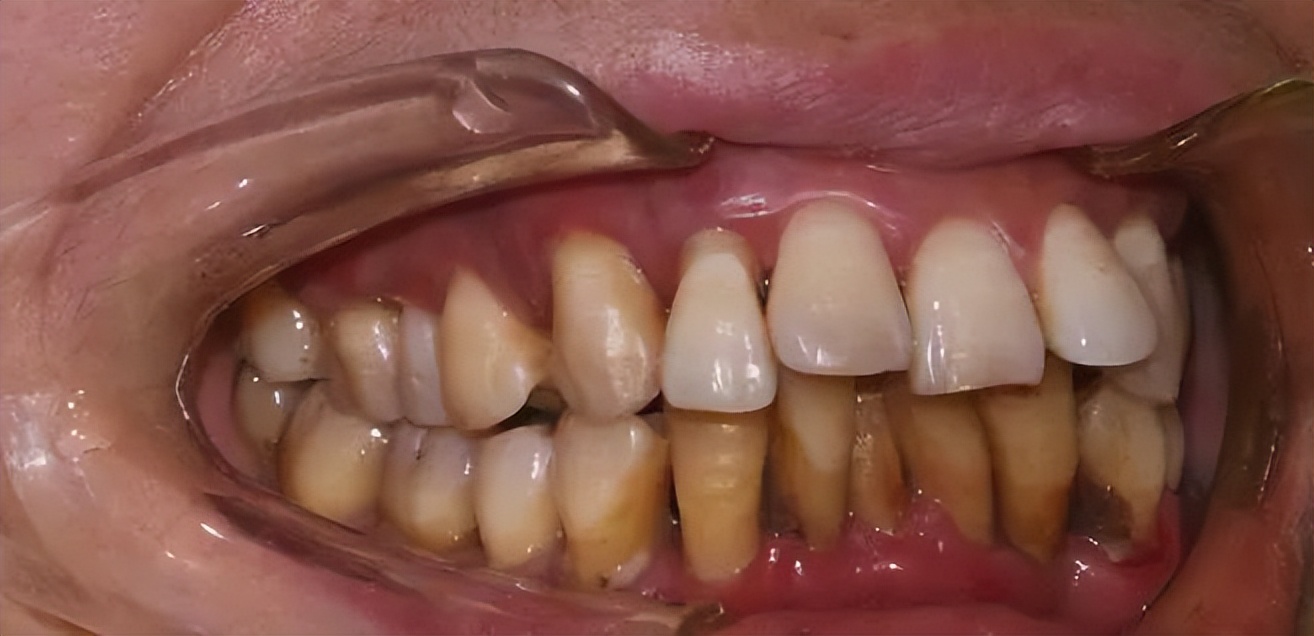

牙结石形成时间比较长,主要是由所吃的食物残渣软垢附着在牙齿上,堆积在牙龈沟内,没有及时刷牙清理干净,长期沉积矿化后形成的。牙结石一般附着在牙龈沟内,通常为黄色、褐色、黄白色,质地比较坚硬。

清理办法: 无法通过刷牙进行有效清理,需要到正规的口腔医院进行超声波洁治,清理掉牙结石。

其实牙垢和牙结石之间虽不相同,但是长时间堆积在口内,不进行清理的话,反复刺激牙龈,引起牙龈红肿出血、发炎的话,容易引起牙周疾病的发生,从而导致牙齿出现松动脱落。